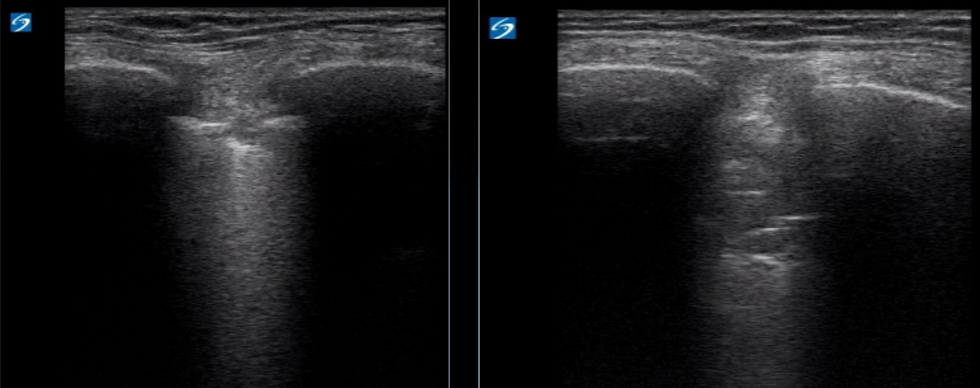

Right chest subpleural changes

Right chest air bronchograms on POCUS

POCUS scan did not show B line burden suggestive of acute pulmonary edema, instead dynamic air-

bronchograms were seen on the right chest which are highly suggestive of pneumonia. In under 30 mins post registration she had antibiotics tailored to source. Later in her blood tests revealed WCC 19.7 x10^9/L, neutrophils of 17 x10^9/L and CRP of 238.

Ultrasound has been shown to be superior to CXR in several studies to identify pneumonia. Ultrasonographic features of pneumonia are dynamic air-bronchograms, focal B lines, sub-pleural consolidation, effusion & hepatization of the lung.